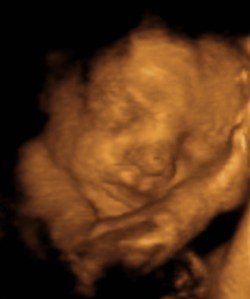

NOSE! Just look at that little pinchable nose! Here we are, at 29 weeks, and believe it or not, there appears to be a REAL baby in my belly! WHOA! talk about sci-fi crazy talk! She’s got a full head of hair, no you can’t see it….that black stuff that might look like hair, is actually her favorite pillow…my bladder. But she has, little hands and feet, pouty lips and appears to be a super cuddler! YAY!

OMG OMG OMG – how exciting!! I'm so happy these turned out SO well. Beautiful baby girl for an amazing set of parents. Can't wait to meet her!

She is SO cute!!!!! yay for baby!